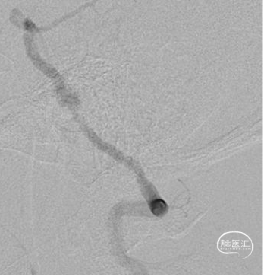

0.014 Synchro微导丝携Fastrack微导管至L-P1,引入4mm*20mm Tubridge血流导向密网支架。

3

Tubridge血流导向密网支架释放,回拉定位,逐步推挤释放支架。

4

释放完毕后跟进支架导管,回收输送导丝,微导丝成袢行支架内按摩。